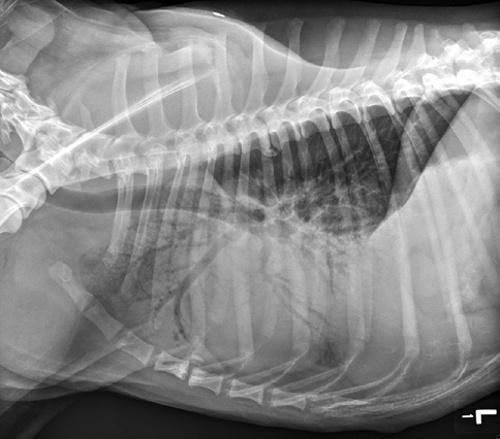

Figure 1.2 Lateral thoracic radiograph showing cranioventral pulmonary infiltrates creating an alveolar pattern consistent with aspiration pneumonia.

depression, pale mucous membranes, dyspnea, crackles or increased bronchovesicular lung sounds, or decreased lung sounds ventrally (pleural effusion) or dorsally (pneumothorax), and cyanosis. Patients with diaphragmatic hernia may have decreased lung sounds dorsally or ventrally. Cyanosis is only seen with severe hypoxemia (at least 5 g/dl of deoxygenated hemoglobin), and thus the absence of cyanosis absolutely does not rule out hypoxemia. In anemic animals, cyanosis is unlikely to be detected due to decreased hemoglobin concentration, and therefore should not be relied upon to diagnose hypoxemia [8].